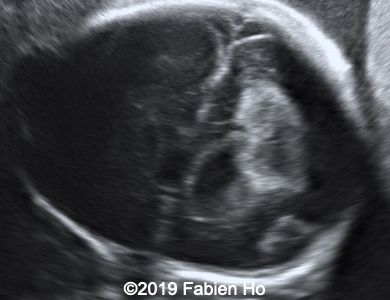

Images 1-3: in the left frontal lobe, hyperechoic with hypoechoic center lesion within the deep and periventricular white matter. Interestingly, this lesion has no mass effect on the lateral ventricle, and it has smooth margins.

Images 4-11, fetal brain MRI at 28 weeks: the left frontal lesion hence shows DWI hyperintensity, with T2* and T1 peripheral hyperintensity: ischemia with peripheral subacute hemorrhage. Note also that there is an associated blood clot in the left lateral ventricle. There is no obvious mass effect, nor peripheral edema. All these findin>gs are very suggestive of a clastic lesion.

Our US examination at 27 weeks of pregnancy revealed the following anomalies, and then we decided to performed an fetal brain MRI at 28 weeks of pregnancy.